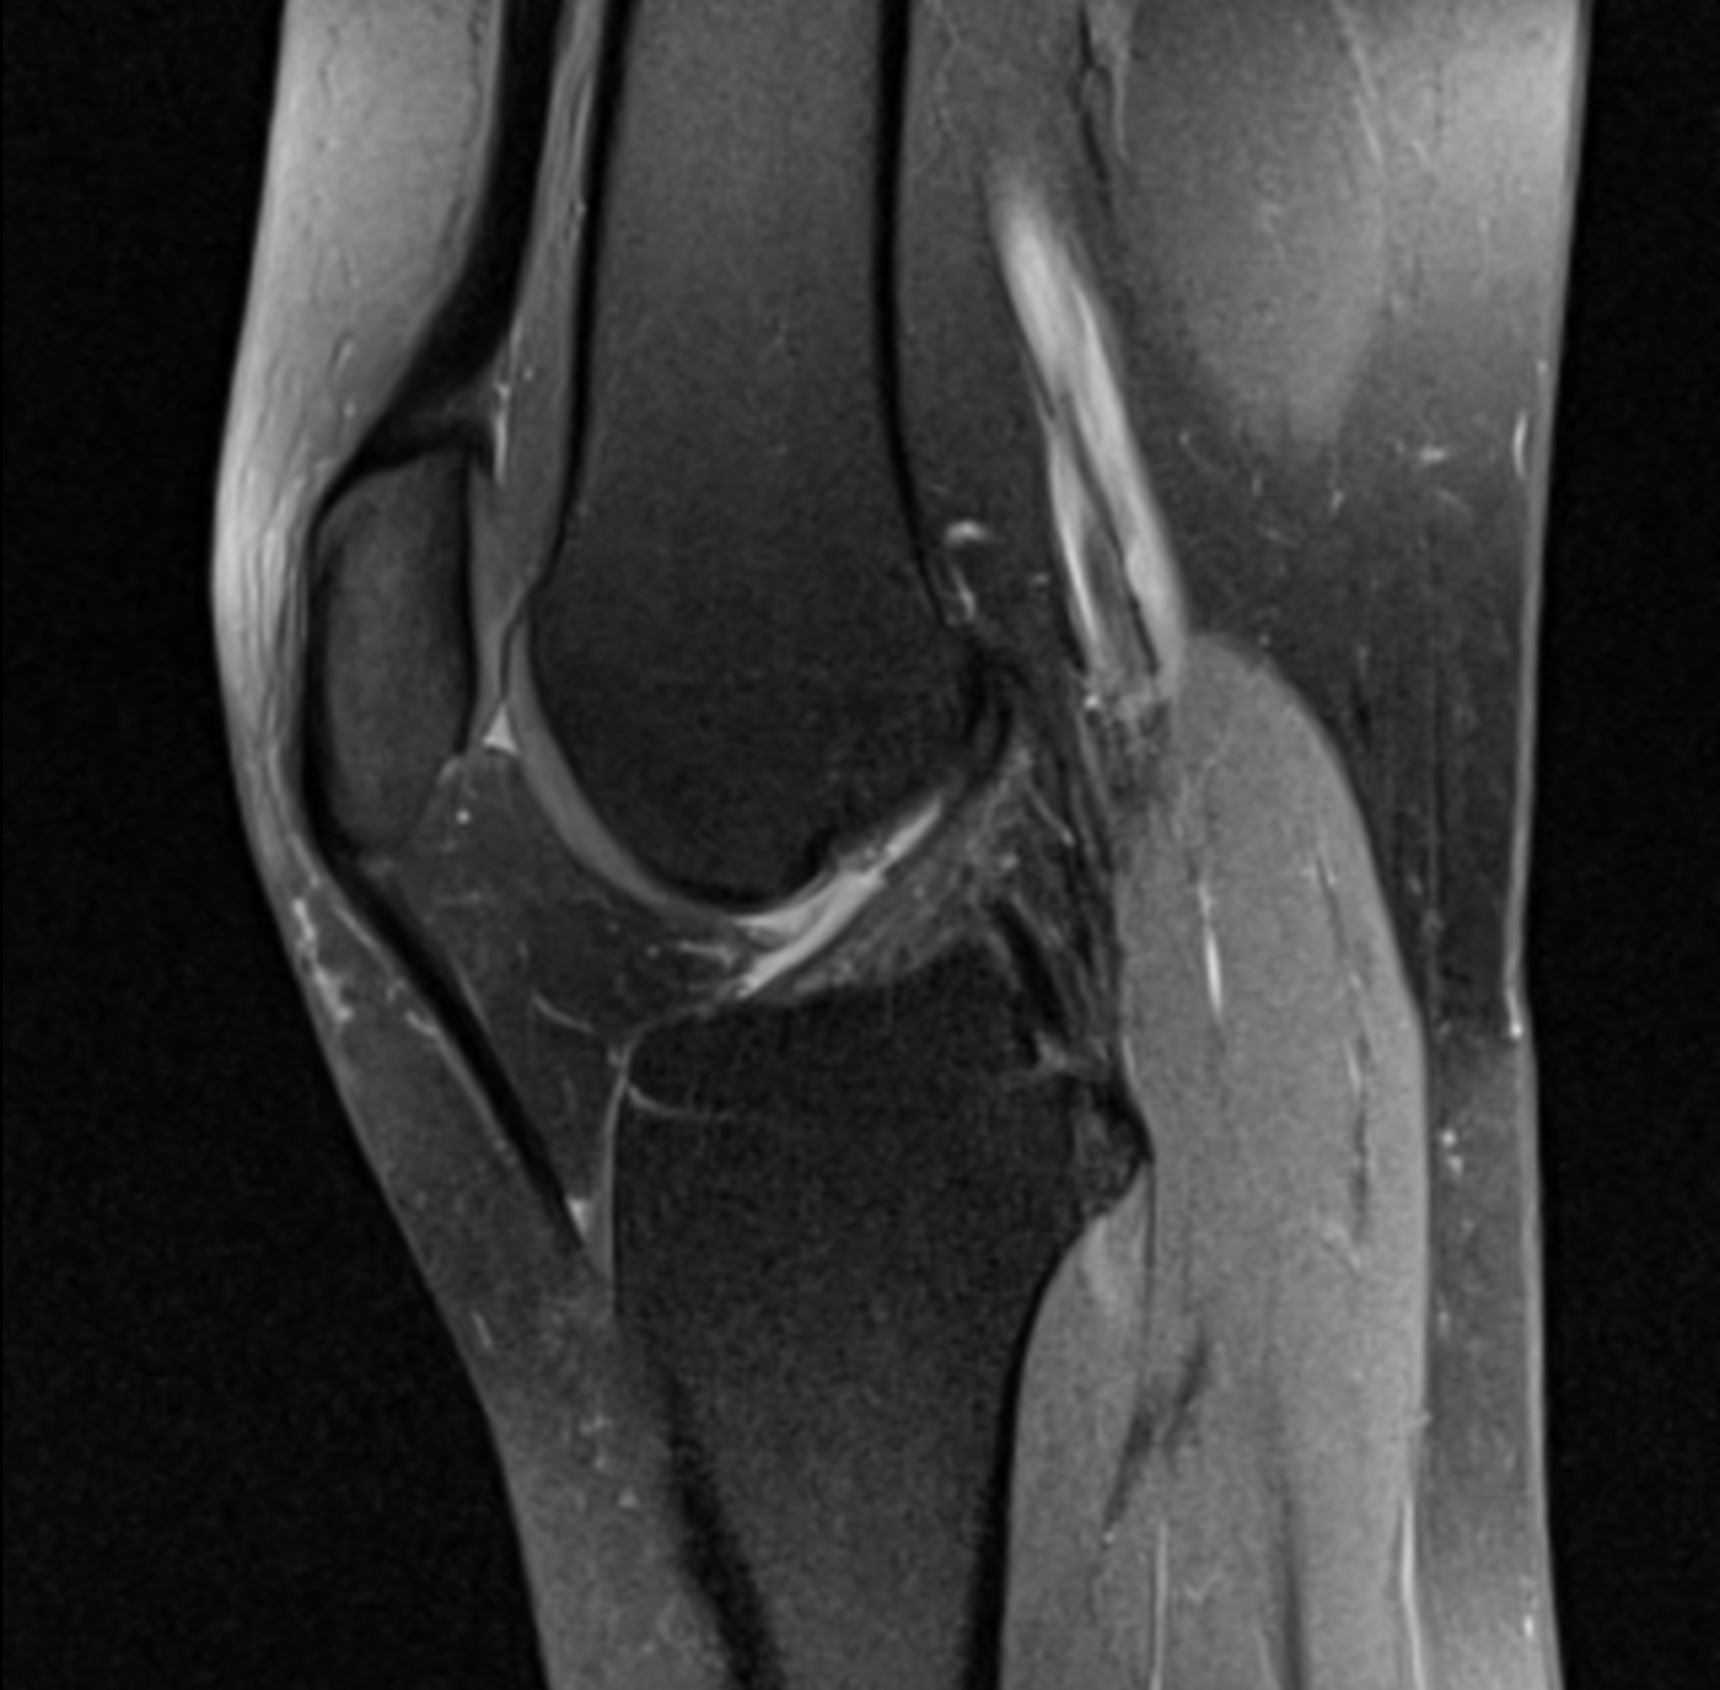

RM de rodilla

Nuestro examen de resonancia magnética de rodilla detecta, vigila daños en el músculo, el cartílago o ligamentos de la rodilla. Tambien dolor de rodilla que no mejora y su inestabilidad.